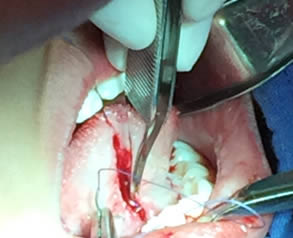

• Se pasa una sutura sin anudar en la punta de la lengua para traccionar la misma y facilitar las maniobras quirúrgicas. Posteriormente se utilizan dos pinzas de mosco, una curva y una recta pinzando el frenillo en su borde superior e inferior para limitar sus bordes. Figuras 3 y 4.

Figura 3. Sutura sin anudar en punta de la lengua

Figura 4. Pinzado del frenillo